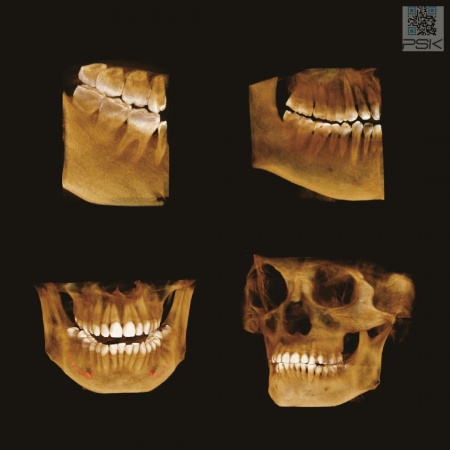

Аппарат базовой комплектации оснащается зоной сканирования 16×8 см. Имея аппарат с зоной сканирования 16×8 см возможно произвести несложный апгрейд для увеличения зоны сканирования до 16×14 см без замены аппарата.

70 мкм в Эндодонтическом режиме 3,5×4 см

Высокотехнологичный детектор с самым высоким разрешением в классе – 70 мкм. Позволяет различить даже самые мелкие анатомические образования и облегчит постановку диагноза в сложных случаях. А вместе с применением алгоритма SMARF инородные тела из металла не испортят качество снимков.